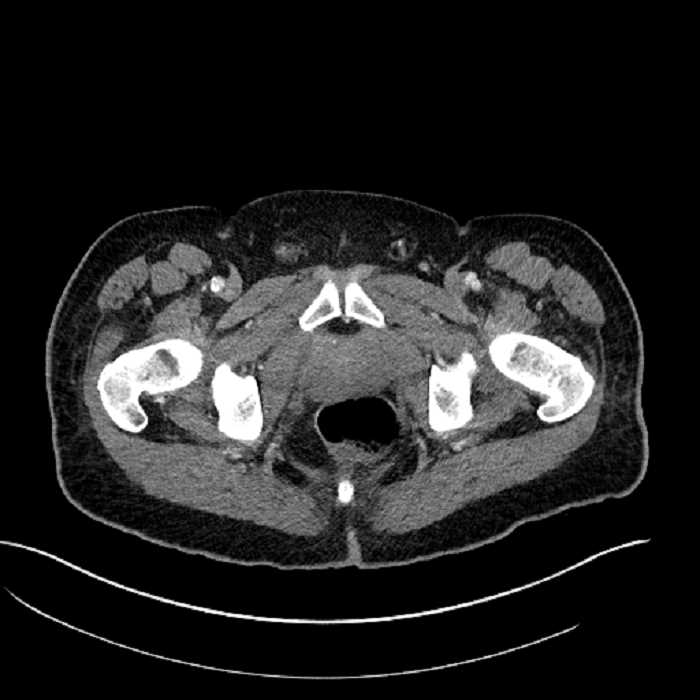

• High grade stenosis of the left common iliac artery, with the left internal and external iliac arteries remaining patent

Acute sigmoid diverticulitis complicated by a small contained perforation and a large abscess in the right hepatic lobe. Additional small subcapsular abscesses along the anterior margin of the left hepatic lobe.

High grade stenosis of the left common iliac artery. The left external and internal iliac arteries are patent.

Hepatic abscess showing the double target sign with low density internally surrounded by a thin inner enhancing rim (red arrow) and ill-defined outer low density rim (yellow arrow). Blue arrow indicates an internal septation. Red arrows: additional smaller subcapsular abscesses. Red arrow: focal contained perforation associated with diverticulitis.